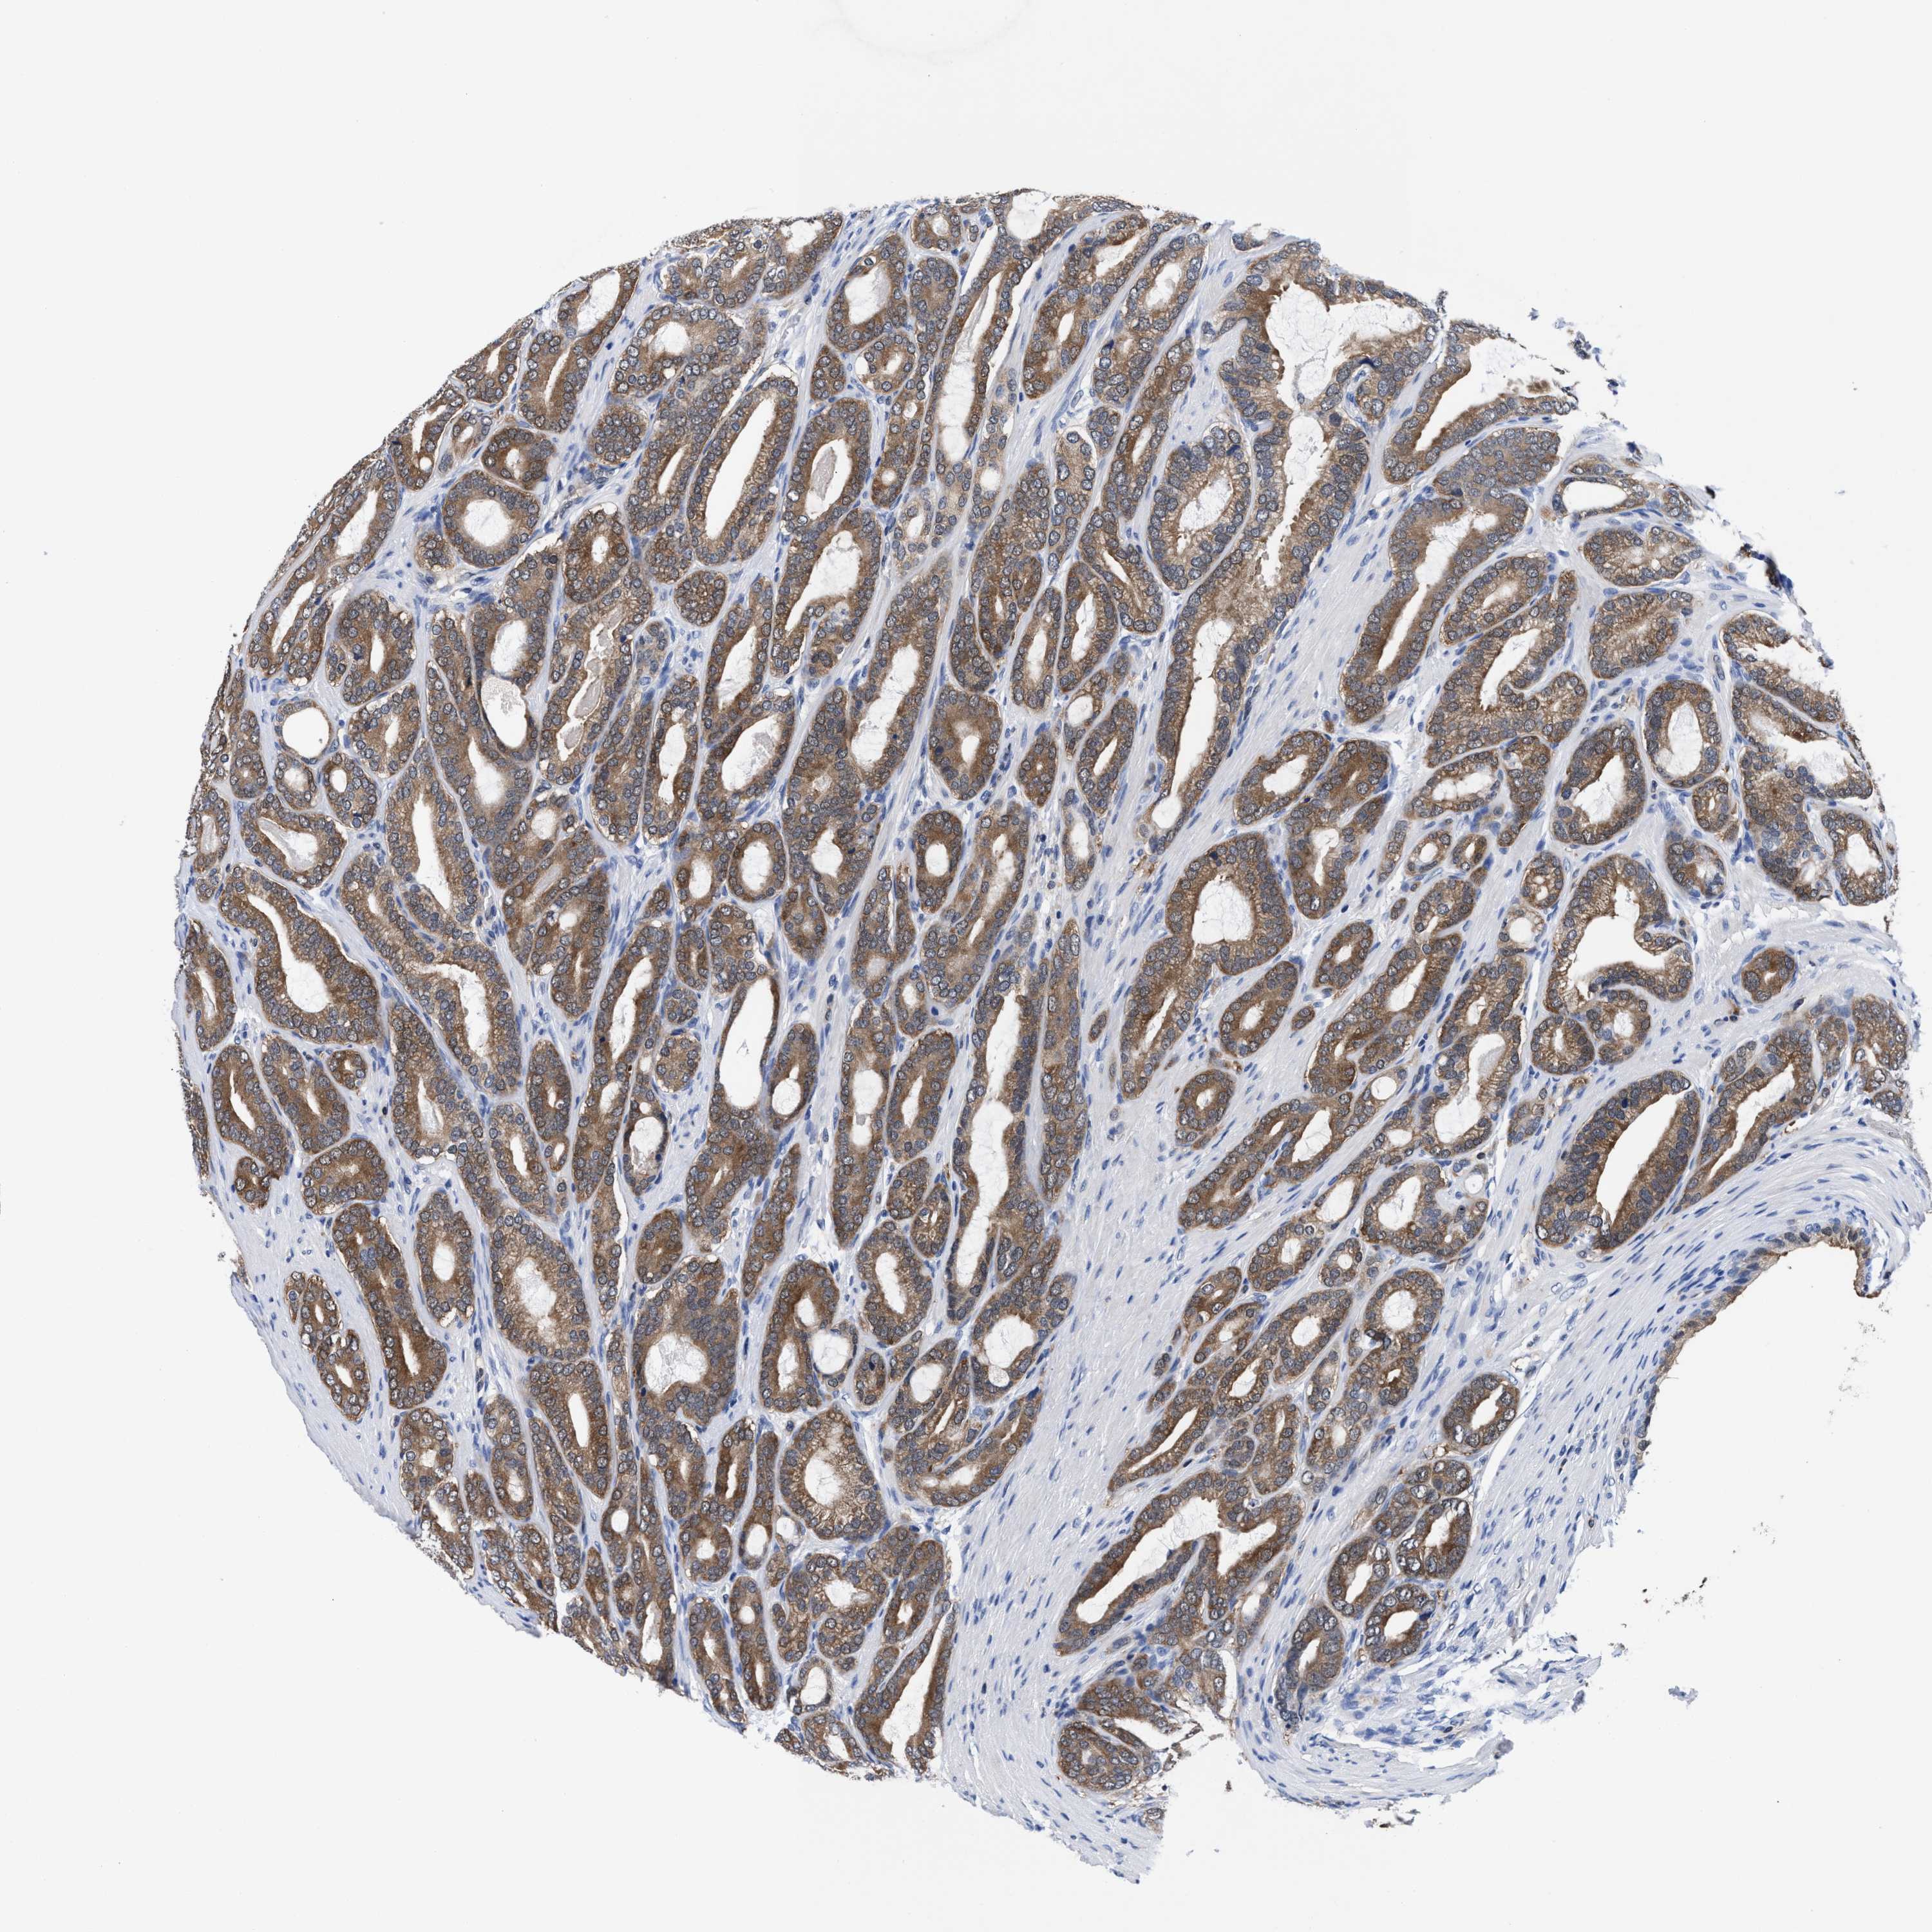

PROSTATE CANCER - Protein expressioni

A mouse-over function shows sample information and annotation data. Click on an image to view it in a full screen mode. Samples can be filtered based on level of antibody staining by selecting one or several of the following categories: high, medium, low and not detected. The assay and annotation is described here.

Note that samples used for immunohistochemistry by the Human Protein Atlas do not correspond to samples in the TCGA dataset.

Antibody stainingi

Antibody staining in the annotated cell types in the current human tissue is reported as not detected, low, medium, or high, based on conventional immunohistochemistry profiling in selected tissues. This score is based on the combination of the staining intensity and fraction of stained cells.

Each image is clickable and will lead to virtual microscopy that enables deeper exploration of all samples and also displays staining intensity scores, fraction scores and subcellular localization as well as patient and tissue information for each sample.

HPA022434

HPA022953

HPA022959

HPA028758

CAB007783

Adenocarcinoma, High grade

Adenocarcinoma, Low grade